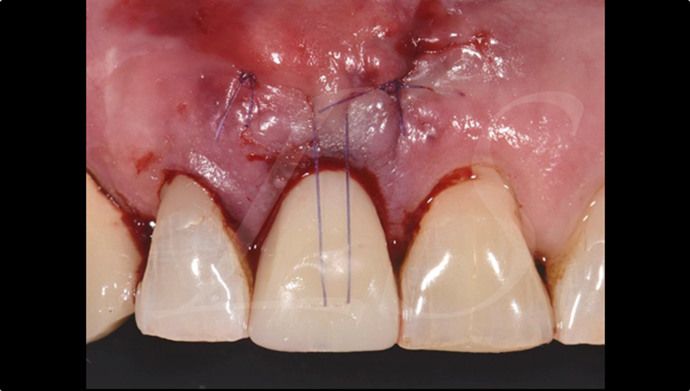

“ One implant /One tooth/ One hour step-by-step

+ associated connective graft ”

Clinical case: EImmediate implant placement & loading of #35 extraction socket with defect

- Courtesy of Dr. Kwang Bum Park, Korea -